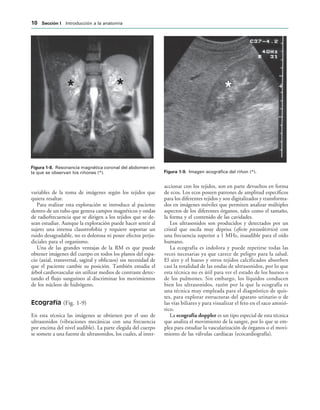

Resonancia magnética (Fig. 1-8)

Es una técnica que permite obtener imágenes del cuerpo

en cualquier plano del espacio sin someterle a radiaciones

ionizantes5

. Permite diferenciar las estructuras anatómicas

mejor que cualquier otra prueba radiológica. Además,

permite emplear contraste con el fin de aumentar la defi-

nición de diferentes estructuras corporales.

IGURA   Resonancia magnética coronal del abdomen en

la que se observan los riñones (*). IGURA   Imagen ecográfica del riñon (*).